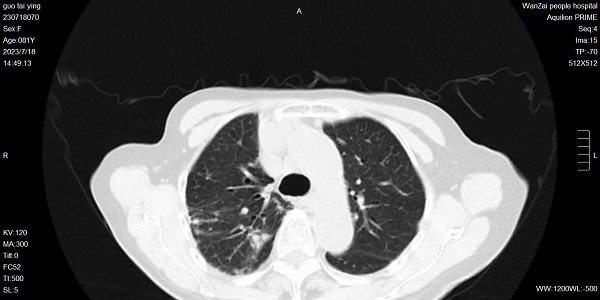

近日,宜春学院第一附属医院 万载县人民医院呼吸与危重症医学科通过电子支气管镜肺泡灌洗液病原靶向测序(tNGS)确诊一例胞内分枝杆菌,即非结核分枝杆菌的一种,予盐酸乙胺丁醇、利福平胶囊、阿奇霉素胶囊等药物治疗,取得满意效果。提到肺结核,大家并不陌生,但提及肺非结核分枝杆菌病,大家却很陌生,它与结核病的临床表现非常相似,且难以分辨。一起来了解吧~什么是非结核分枝杆菌?非结核分枝杆菌(non-tuberculosis myco...